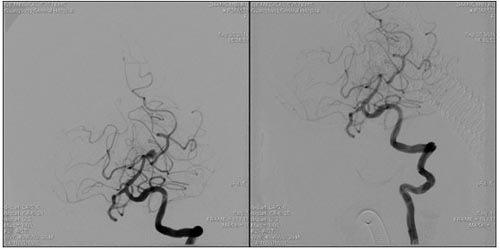

小脑动静脉畸形栓塞术前 小脑动静脉畸形栓塞术后